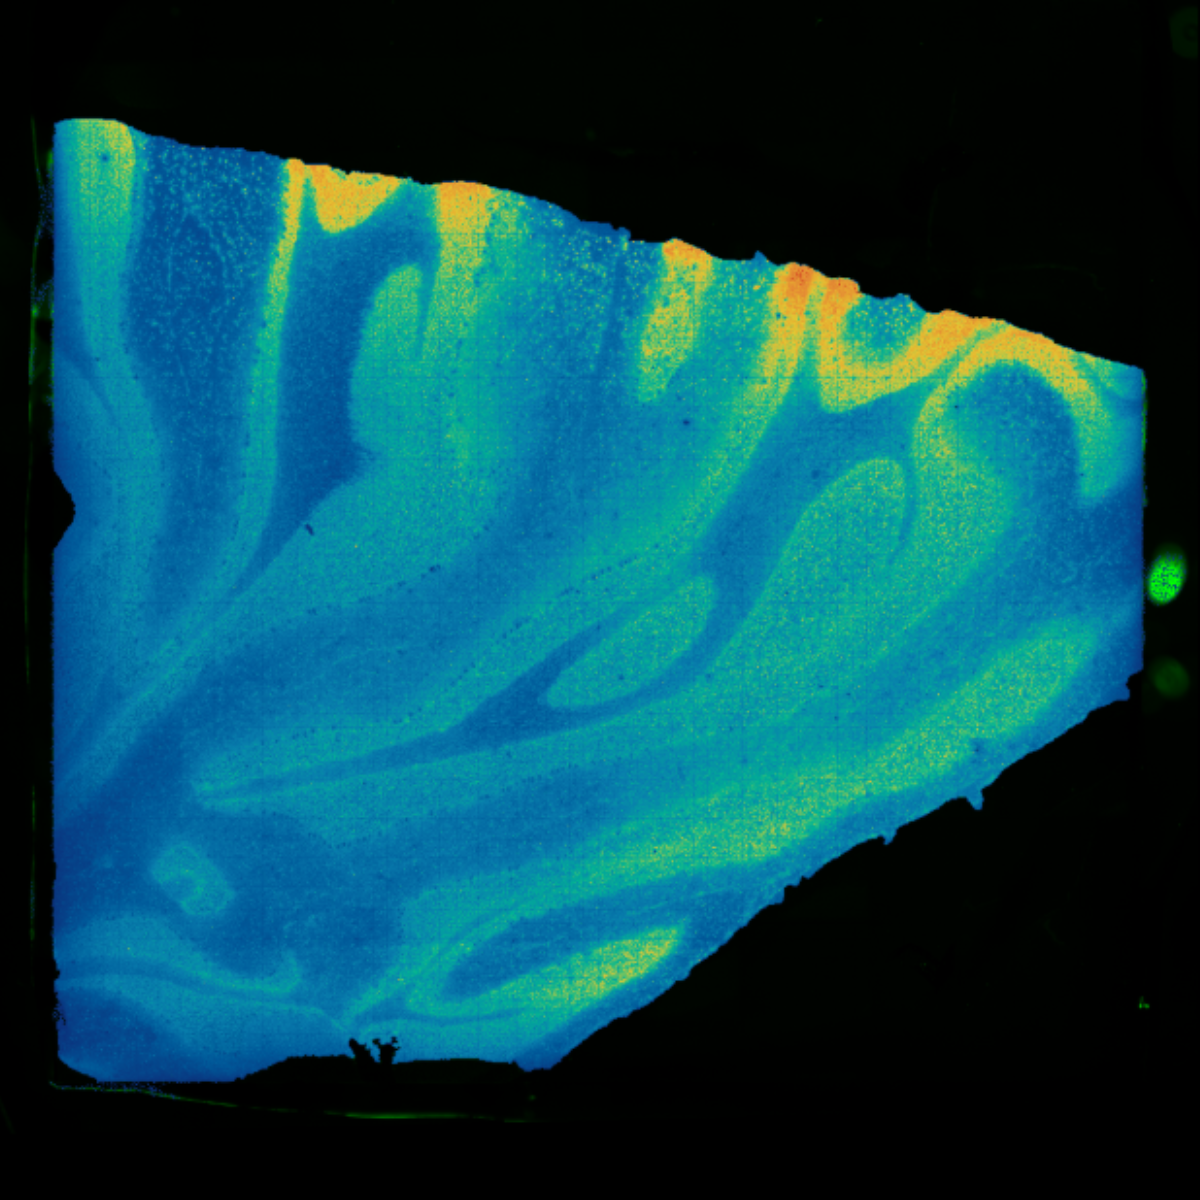

Sample Type: FFPE

Sample Origin: monkey brain

Platform: Stereo-seq OMNI